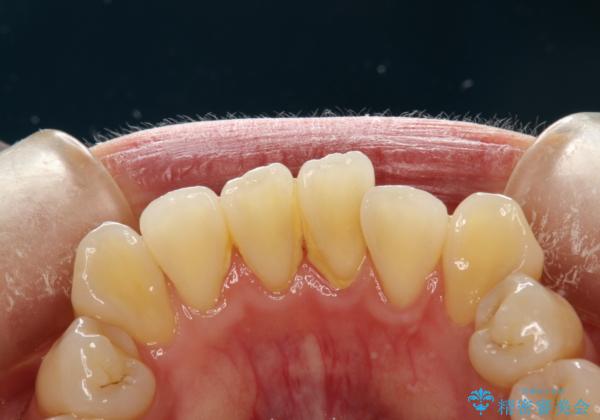

- これから矯正治療を始めるため、今の状態でも歯をきれいにしておきたいとのことでした。PMTC60分コースを行いました。

プラーク(細菌の塊)や歯石がたまると歯の表面はザラつきいてきます。そのザラつきは歯周病や虫歯菌の棲家となります。そのまま放置すると、歯肉が腫れてきたり、歯肉から出血したり、口臭が強くでたりします。とくに歯肉の境目は、歯磨きで汚れを除去することが難しく、プラーク(細菌の塊)や歯石が溜まりやすい場所です。

歯並が、がたついている場合はなおさら汚れが溜まりやすいです。矯正治療前や矯正中、定期的にPMTCをすることで、矯正治療中の歯肉トラブルを防ぐことにつながります。